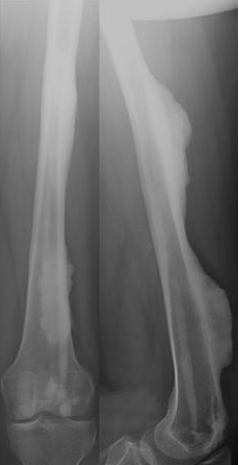

Diagnosis?

Melorheostosis

Periosteal formation of new bone

Looks like dripping candle wax

Benign but painful

Symptomatic treatment ± excision